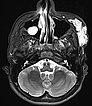

Axial, T2-weighted fat-suppressed MRI of the face. The venous malformation appears typically very hyperintense here too. No expansion into the depth.

Axial, T2-weighted MRI of the face (without fat suppression). The venous malformation is highly hyperintense and shows fluid-fluid levels.